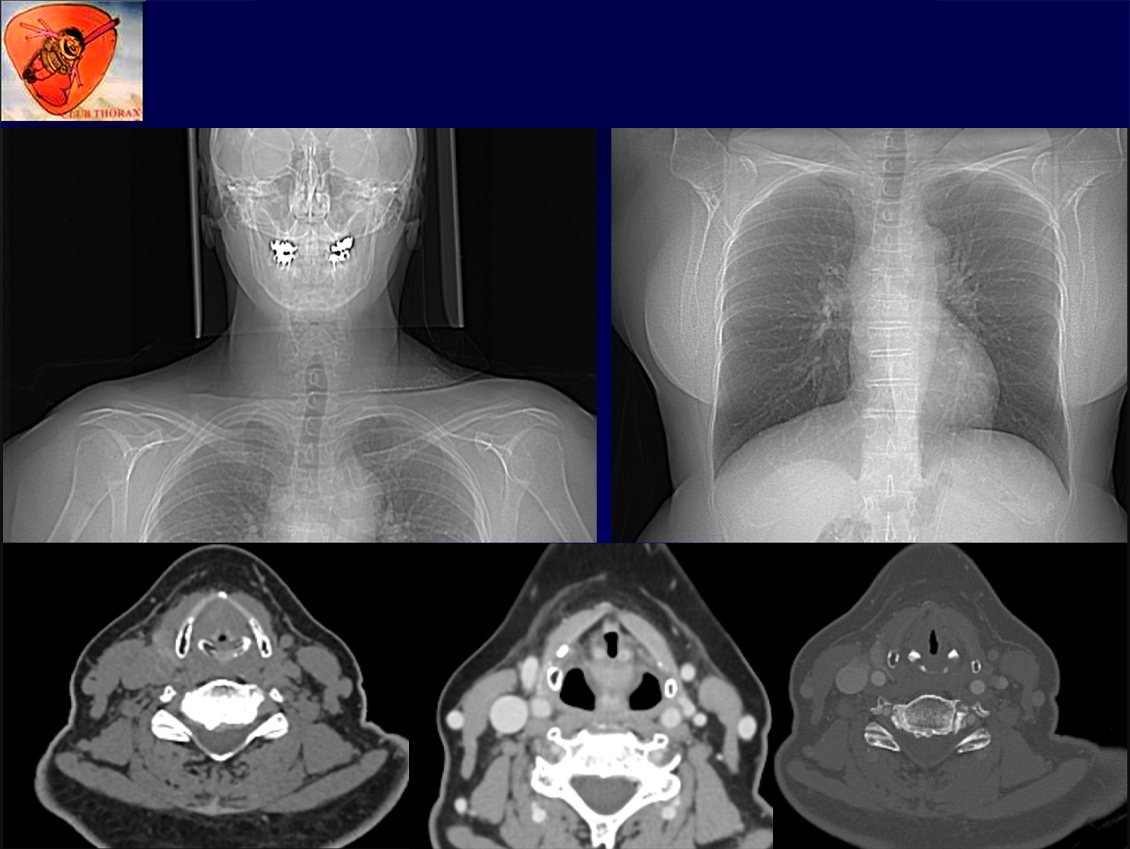

Patiente 29/12/1957 non fumeuse,

ATCD d’EOA T1N0M 1/3 ant corde vocale D TTT : IRX seule, Orthophonie OK

Pas d’Asthme, pas de wheezing.

Pas d’ADP cervicale, pas de dysphonie.

Bilan TDM de suivi à 2 ans, aucun signe fonctionnel clinique. Ex clinique normal.